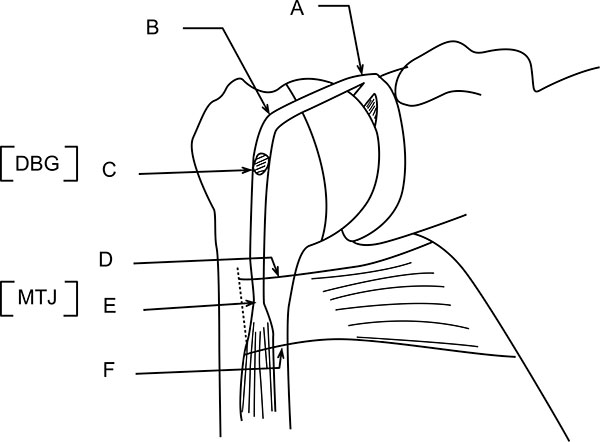

Using a proximal delto-pectoral skin incision, the distal part of the bicipital groove (DBG) is exposed, retracting the deltoid-pectoral complex superolaterally with a Hohmann retractor, while the short head of the biceps brachii and the coracobrachialis muscles are retracted medially with a right angled retractor. Adequate visualization of the distal part of the biceps groove is paramount. One should avoid vigorous medial retraction to protect the musculocutaneous nerve. The site for drilling is identified at the distal-most aspect of the biceps groove (Fig. 2).

If the proximal end of biceps tendon could not be traced with this approach, then we need to make another 3cm incision in the subpectoral region, centered over the inferior border of the pectoralis major tendon. Superficial soft tissue is dissected to expose the fascia over the inferior border of the pectoralis major muscle. The fascia is incised from the lower border of the pectoralis muscle distally along the coracobrachialis and biceps muscles. The longitudinal, white tendon of the biceps tendon is identified and pulled out of the incision (Fig. 3A).

At this stage, we go back to our first incision site to prepare the tenodesis site. The distal part of the bicipital groove (DBG) is identified and cleared off soft tissues. A 2.7mmx 15” guide wire is drilled at an angle of 45º through the center of DBG. Care should be taken to avoid skydiving off the edge of the humeral shaft (Fig. 3B). The guide wire should be stopped as soon as the pin penetrates the posterior cortex (Fig. 4A). This is followed by drilling the anterior cortex over the guide wire with a calibrated cannulated drill, the size of which is the same as the measured diameter of the tendon (in our case, a 7-mm drill for a 7-mm tendon) (Figs. 3C, 4B). Care is taken to only drill up to the posterior cortex without engaging the cortex or plunging through. Depth of this bone tunnel is measured with the aid of a calibrated drill (TD- Tunnel Depth). Usually it is around a 20-25mm tunnel in adults. The hole should be lined up at the base of the biceps groove and cleared of soft tissue. Finally, the posterior cortex is drilled through with a 4.5-mm drill to allow for the passage of the cortical button (Fig. 4C).

Hereby, we describe a novel technique to estimate the required tendon length and calculate the tendon resection length (Figs. 5, 6, 7). Jarrett et al. [6], found that the musculo-tendinous junction (MTJ) of the biceps lies 22 mm distal to the upper border of the pectoralis major tendon and 31 mm proximal to the lower border of the pectoralis major tendon. The MTJ is identified and marked (A) (Fig. 6). Another point (marked B) Fig. (6) lies 22mm above the MTJ. The tension on the tendon is released, ensuring that mark B is at the upper border of the pectoralis major tendon. At this point, a stay suture knot is applied through the biceps tendon and the upper border of the pectoralis major tendon (mark B).

Now, the tendon end to the DBG is retrieved using the smallest size Foleys catheter. Keep the tendon over the tunnel, without any kinking, and mark (C) on the tendon at DBG (Fig. 6). Make another mark (D) on the tendon at a distance equal to measured tunnel depth (TD) (Fig. 6). Hence, the required tendon length for this procedure is A-D (Fig. 6). The tendon is resected at mark D. Now, the tendon end is pulled back through distal incision for suturing. This is because it is easy to suture the tendon when we have enough length of tendon to hold and know the rotational alignment of the tendon.